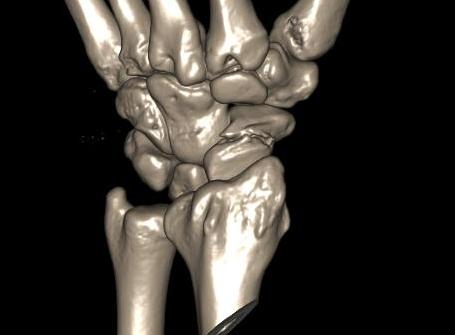

Anatomy

Scaphoid is greek for boat

- shaped more like a twisted peanut

- majority is articular cartilage except for dorsal ridge

- dorsal ridge is site of entry of majority of blood supply